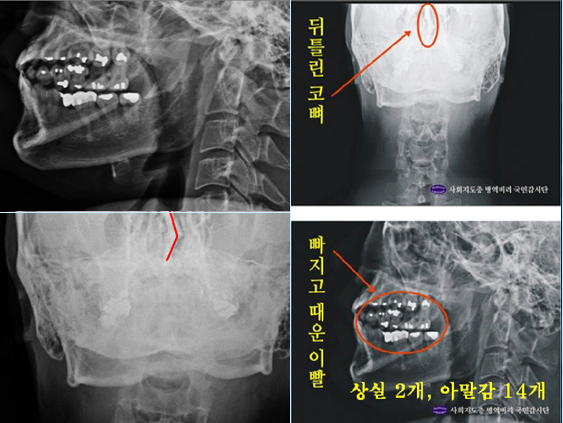

양승오 박사 재판을 심리 중인 서울중앙지법 27형사부(재판장 심규홍 부장판사)는, 최근 이 사건 핵심 증거 중 하나인 박주신씨 명의의 엑스레이 3개(자생병원·공군훈련소·비자발급용)에 대한 검찰 및 피고인들의 감정신청을 받아들였다.

감정 대상이 된 박주신씨 명의의 엑스레이는 2011년 12월 촬영된 자생병원 엑스레이, 박주신씨가 2011년 공군에 입소하면서 본인 확인 후 촬영한 엑스레이, 지난해 7월 영국 출국에 앞서 비자 발급을 위해 연세대 세브란스병원에서 새로 촬영한 엑스레이 등 3개다.

이들 엑스레이를 판독한 국내 의료진들은 “2011년 12월 자생병원에서 찍은 엑스레이에서는 우측 제1늑골에 석회화 소견이 발견되고, 흉추 1번 극상돌기 역시 수직방향으로 배열돼 있지만, 공군 엑스레이와 비자발급용 엑스레이에서는 석회화 현상이 발견되지 않았고, 극상돌기 역시 오른쪽 방향으로 배열돼 있다”고 지적하고 있다.

나아가 의사들은 박주신씨 명의의 엑스레이에 대한 비교·판독 결과, ▲흉추 1번, 경추 7번의 추궁판과 극돌기 밑단의 형태 ▲견갑골 견봉의 두께 ▲견갑골 오구돌기와 관절와(關節窩) 평면과의 각도 등에서 차이점이 발견된다고 지적하고 있다.

박주신씨 병역비리 의혹의 핵심 증거,

의문의 엑스레이 속 피사체는 누구?

2011년 박주신씨에 대한 병역비리 의혹이 처음 불거진 뒤 지금까지 박주신씨의 신체를 촬영한 것으로 알려진 엑스레이는 모두 3개가 있다.이 가운데 언론을 통해 널리 알려진 자생병원 엑스레이(촬영일자 2011년 12월 9일)는, 박주신씨 본인이 아닌 제3자의 신체를 촬영한, 이른바 ‘대리신검자 엑스레이’라는 의심을 받고 있다.

- ▲ 박주신씨 명의의 자생병원 엑스레이. ⓒ 뉴데일리DB

반면 지난해 12월부터 시작된 양승오 박사 등 시민 7명에 대한 공직선거법 위한 공판을 통해 새롭게 밝혀진, 박주신씨의 ‘공군훈련소 입소 당시 엑스레이’(촬영일자 2011년 8월 30일, 이하 공군 엑스레이)와, 주신씨가 ‘비자발급을 위해 촬영한 세브란스병원 엑스레이’(촬영일자 2014년 7월 31일, 이하 비자발급용 엑스레이)는 각각 박주신씨 본인의 신체를 촬영한 것으로 받아들여지고 있다.

-

- ▲ 박주신씨 공군훈련소 입소 당시 촬영된 엑스레이. ⓒ 뉴데일리DB

- ▲ 박주신씨가 지난해 7월 비자발급을 위해 촬영한 엑스레이. ⓒ 뉴데일리DB

이들 세 개의 엑스레이는 모두 박주신씨의 신체를 촬영한 것으로 알려져 있기 때문에, 이들 엑스레이에 대한 판독결과 피사체를 동일인으로 볼 수 없는 유의미한 차이점이 발견된다면, 이는 박주신씨의 대리신검 혹은 영상자료 바꿔치기 의혹을 뒷받침하는 결정적 단서가 된다.

세계적 권위를 인정받은 영상의학 전문의인 양승오 박사(동남권원자력의학원 암센터 핵의학과 주임과장)와 치과의사 김우현씨 등 박주신씨 병역비리 의혹을 주장해 온 시민들은, 위에서 언급한 세 개의 엑스레이에 대한 비교 판독 결과, 이들 엑스레이를 같은 사람의 것으로 볼 수 없는 차이점을 발견하고 이를 재판부에 증거자료로 제출했다.

‘석회화’와 ‘극상돌기’

‘석회화’란 나이가 들어 뼈에 발생하는 퇴행성 증상의 하나로 질병이라고 볼 수는 없지만 한 번 생기면 없어지지 않으며, X-Ray를 통해 확인할 수 있는 것으로 알려졌다.

- ▲ ▲박주신의 자생병원 X-Ray(왼쪽)과 공군 X-Ray(오른쪽). 자생병원의 엑스레이에서는 오른쪽 제1늑골부위에 '석회화'현상이 보이지만 공군엑스레이에선 보이지 않는다. ⓒ 뉴데일리DB

박주신씨의 자생병원 X-Ray를 보면, 오른쪽 제1 늑골부위에 ‘석회화’ 현상이 나타난다. 그러나 주신씨가 공군 입대 당시 찍은 X-Ray에는 이런 모습이 전혀 보이지 않는다.

이런 차이에 대해 양승오 박사의 변호인인 차기환 변호사 등은 "각각의 X-Ray를 찍은 사람이 동일인이 아니라는 것을 입증한다"고 설명했다.

‘극상돌기’의 경우에도 차이점은 명확히 드러난다.

변 호인 측은 “공군에서 찍은 엑스레이와 비자발급을 위해 찍은 엑스레이에서는 피사체의 제 1흉추 극상돌기가 오른쪽으로 휘어있지만, 자생병원에서 찍은 영상에서는 정방향으로 나온다”며, “박주신씨가 공군에 입대해 찍은 엑스레이와 세브란스 공개신검에서 나타난 피사체의 의학적 차이가 명확해 동일인이라고 인정할 수 없다”고 지적했다.

우리가 흔히 등을 만지면, 가운데 뾰족하게 솟아난 부분이 바로 ‘극상돌기’다.

흉추를 비롯해 모든 척추에 존재하며, 흉추에 외상이나 수술, 질병 등이 없었던 근접한 기간 동안 촬영된 엑스레이에서 극상돌기의 형태가 명확하게 다를 경우, 다른 개체라고 판단할 의학적 근거가 된다.